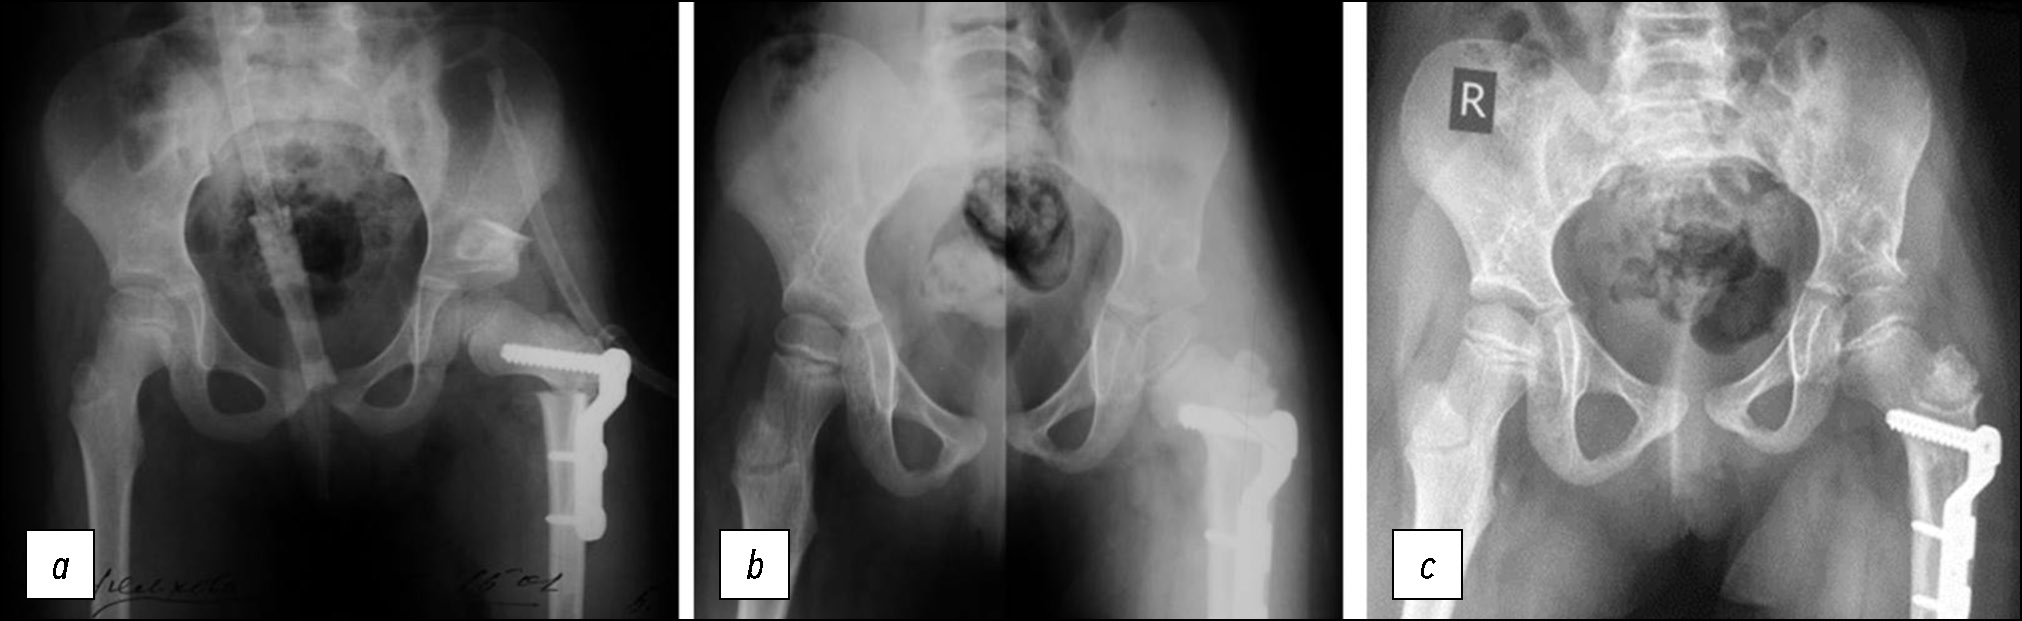

Рис. 4. Рентгенография таза пациентки В.: a — после операции: индекс Reimers 4% (справа), 0% (слева); АИ 23° (справа), 16° (слева); угол Wiberg 23° (справа), 38° (слева), b — через 2 года после операции: индекс Reimers 6% (справа), 0% (слева); АИ 23° (справа), 18° (слева); угол Wiberg 25° (справа), 34° (слева), c — через 3 года после операции: индекс Reimers 4% (справа), 6% (слева); АИ 22° (справа), 20° (слева); угол Wiberg 28° (справа), 32° (слева). АИ — ацетабулярный индекс.

Fig. 4. X-ray of the pelvis of patient V.: a — after surgery: Reimers index 4% (right), 0% (left); AI 23° (right), 16° (left); Wiberg angle 23° (right), 38° (left), b — 2 years after surgery: Reimers index 6% (right), 0% (left); AI 23° (right), 18° (left); Wiberg angle 25° (right), 34° (left), c — 3 years after surgery: Reimers index 4% (right), 6% (left); AI 22° (right), 20° (left); Wiberg angle 28° (right), 32° (left). АI — acetabular index.